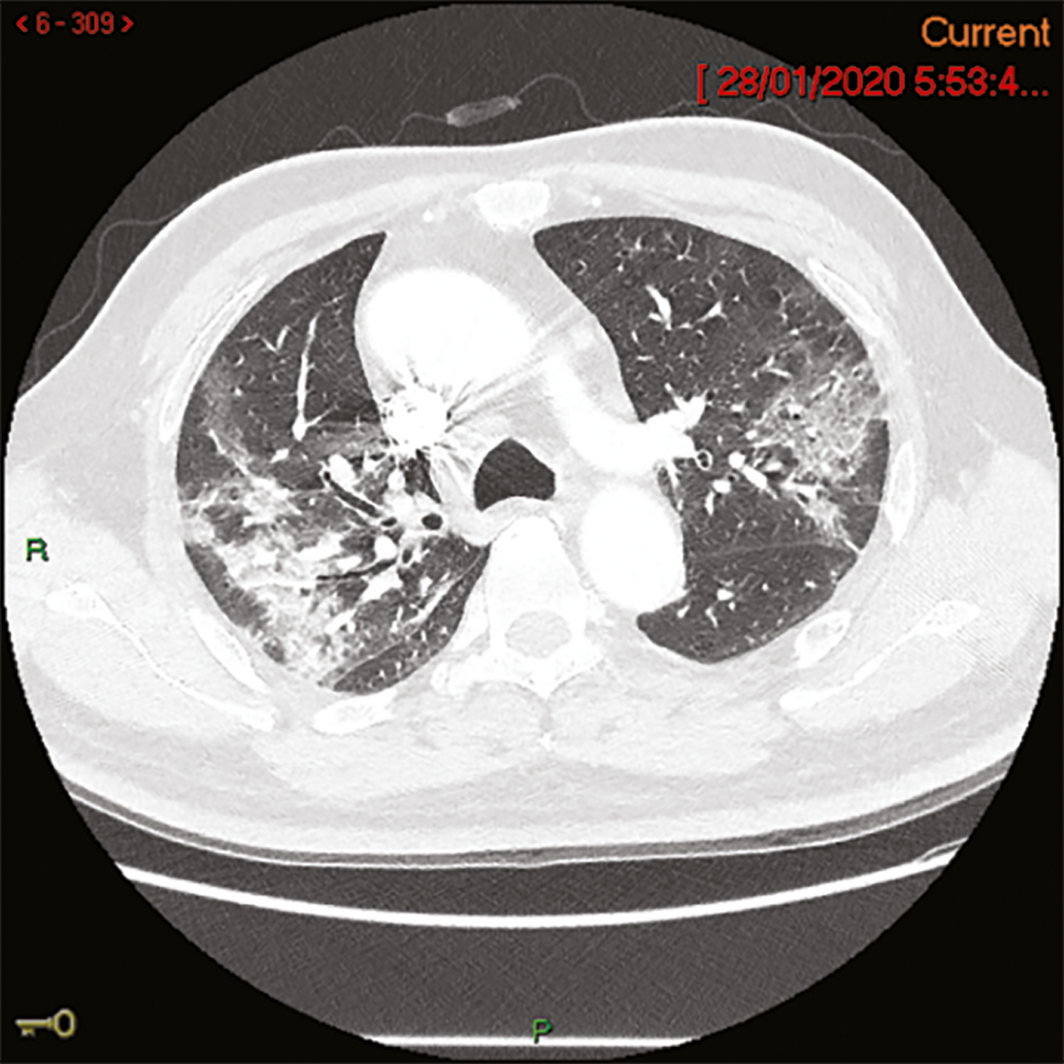

A 58‐year‐old man from Wuhan, China, felt unwell on the day of his arrival in Melbourne (19 January 2020). In China, he had had no contact with live food markets, people known to have COVID‐19, or hospitals. His medical history included type 2 diabetes mellitus, and he had ceased smoking four years previously. He developed fever on 20 January and a cough with sputum production on 23 January; on 24 January, he was admitted to the Monash Medical Centre, Melbourne, from its emergency department with progressive dyspnoea. His temperature was 38.1°C, his heart rate 95 beats/min, and O2 saturation 94% on room air. A chest x‐ray showed subtle ill‐defined opacities in the middle zones bilaterally and in the left lower zone. A thoracic computed tomography scan on admission day four identified extensive ground glass opacities with a peribronchovascular and peripheral distribution in the middle to upper zones of the lungs (Box 1). Full blood examination results included a lymphocyte count of 0.80 × 109/L (reference range, 1.0–4.0 × 109/L). C‐reactive protein concentration peaked on admission day 6 at 182 mg/L (reference range, 0–5 mg/L). Liver function test abnormalities peaked on admission day 12 — alkaline phosphatase, 210 U/L (reference range, 30–110 U/L); γ‐glutamyltransferase, 416 U/L (reference range, 30–110 U/L); alanine aminotransferase, 183 U/L (reference range, 5–40 U/L) — and hepatic steatosis was evident on liver ultrasound. Intravenous ceftriaxone (2 g/day) and azithromycin (500 mg/day) were commenced on admission day 4 to treat potential secondary bacterial pneumonia, although no bacterial pathogen was identified. Low‐flow oxygen (maximum 3 L/min via nasal prongs) was administered until admission day 10. The patient gradually improved; fever, productive cough and dyspnoea resolved by admission day 12, and he was discharged from hospital on 7 February (admission day 15).

Box 1 – Thoracic computed tomography (CT) image of patient on admission day 4